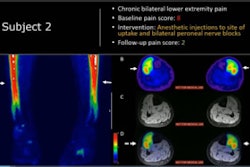

FDG-PET/CT is being increasingly used to evaluate how patients respond to treatment; however, few studies have assessed which imaging method may be superior for selecting patients for surgery, the investigators noted.

According to the analysis, the PPV of FDG-PET/CT for detecting residual disease was 89% compared with 65% for MRI and US-FNA. Moreover, if FDG-PET/CT showed that patients had a complete metabolic response from the treatment, they did not undergo surgery, the authors wrote.

"FDG-PET/CT significantly improved the accuracy of the detection of [pathologic-confirmed residual neck disease], thereby reducing the number of patients undergoing unnecessary SND by 22%," the group wrote.

In addition, the incorporation of FDG-PET into neck surveillance and neck management has long-term cost savings associated with the readmissions, surgical complications, and new surgical interventions needed to treat these complications and rehabilitations after SND, according to the authors.